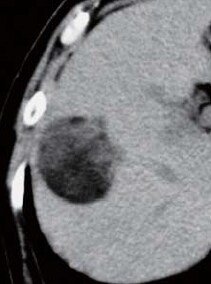

Abdominal CT findings

A tumor 4.4 cm in diameter was found in the posterior segment. Simple computed tomography (CT) showed intensely low absorption. Contrast CT showed hypovascularity with no dark staining even in the arterial phase, and a low-absorption region in the equilibrium phase. Slight protrusion was suspected at the tumor margin.

Simple CT

Contrast CT arterial

phase

Contrast CT equilibrium phase